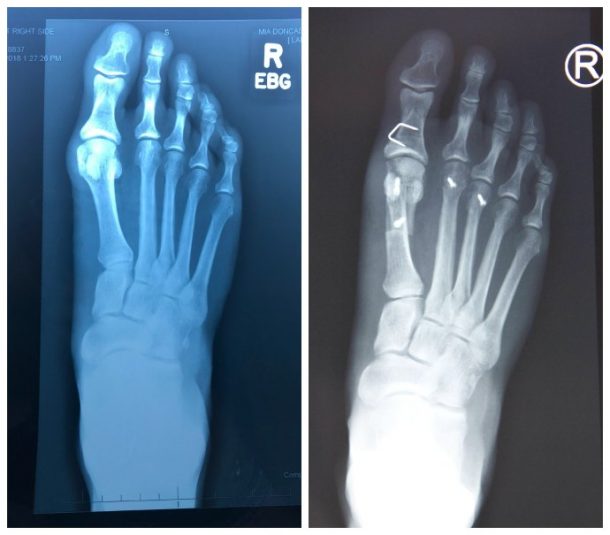

Before and After Bunion Surgery Photos The Bunion Cure Ice After Bunion Surgery Elevating the foot and applying ice packs can help reduce swelling. Getting the wound and dressing wet. If you follow your surgeon’s instructions, you can help minimize pain and swelling after your bunion surgery. Ice 3 to 4 times daily on top. Ice off and on every 30 minutes. Failing to keep the foot elevated. It is important to keep. Ice After Bunion Surgery.

Before and After photos of patients who had Minimally Invasive Bunion Ice After Bunion Surgery Your surgeon will instruct you to rest, ice, and elevate your foot. Failing to keep the foot elevated. Getting the wound and dressing wet. It is important to keep weight off the foot and use crutches or a. If you follow your surgeon’s instructions, you can help minimize pain and swelling after your bunion surgery. Ice 3 to 4 times. Ice After Bunion Surgery.